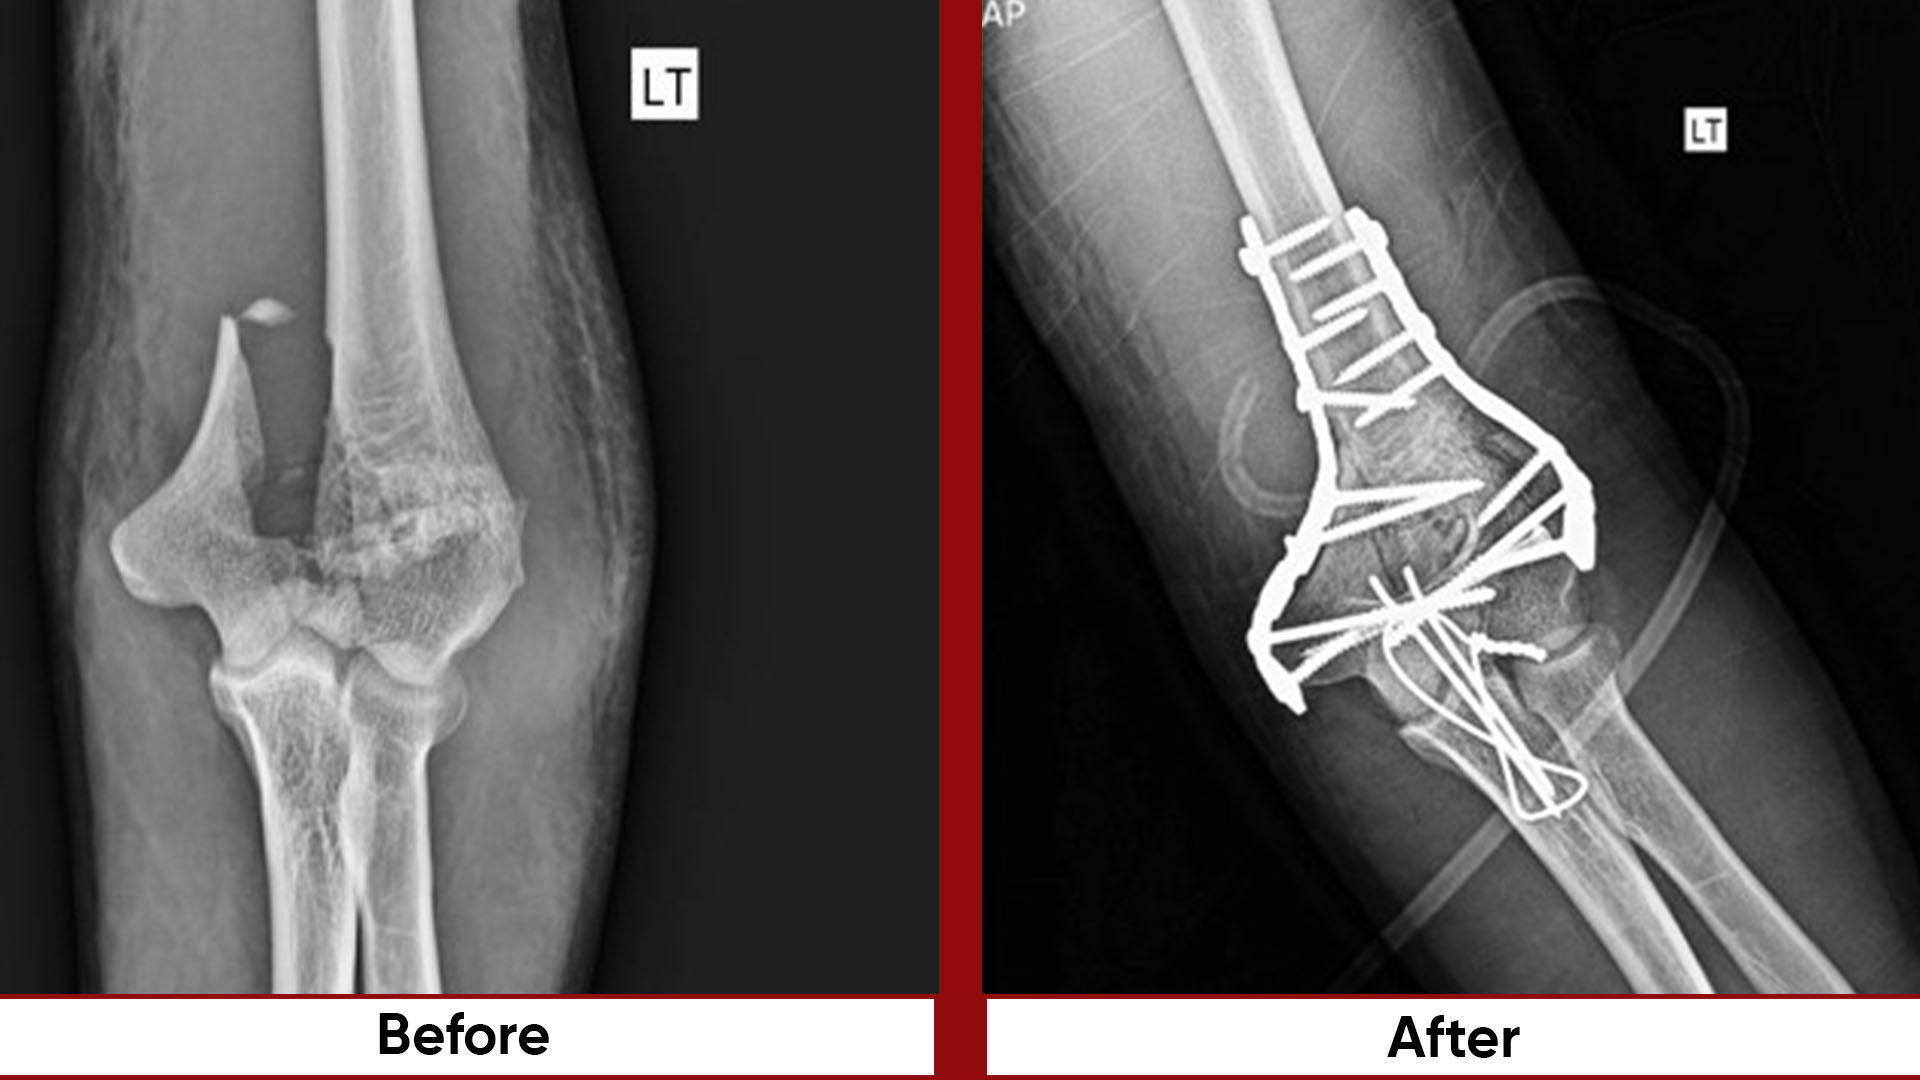

• Fracture Management (simple and complex trauma)

• Pelvic & Acetabular Fracture Fixation

• The department has its own Orthoplastics department and the busiest SIGN Trauma set up.